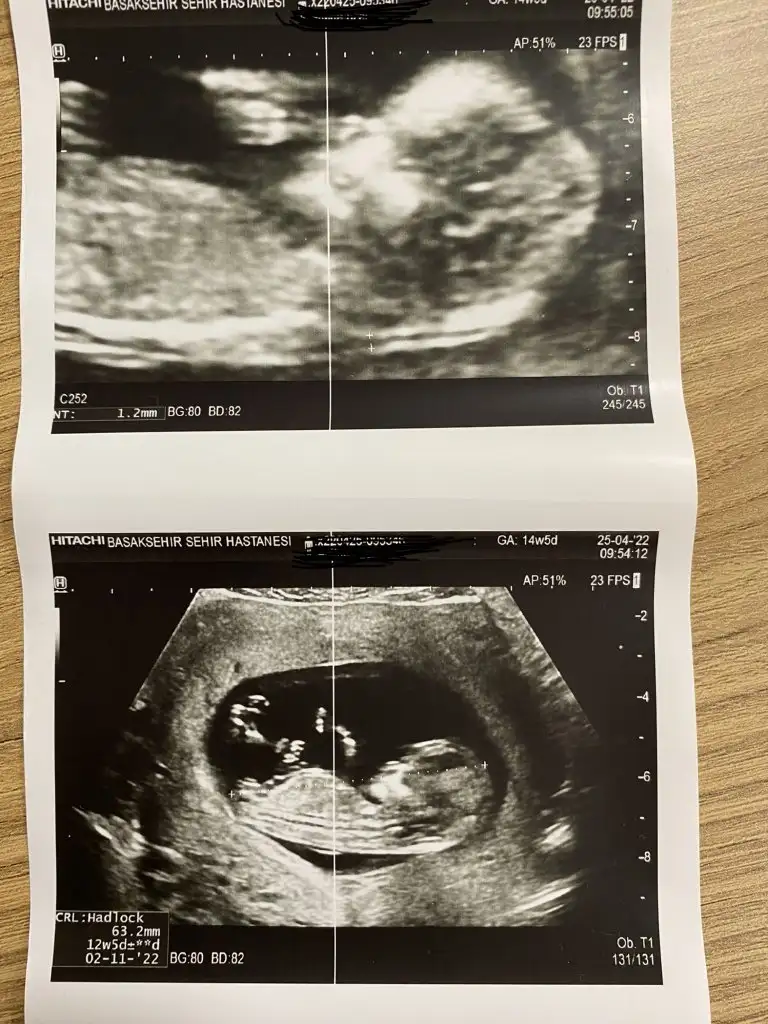

Karından ultrason 12+5 küçük olan resim ise 10 haftalık :)